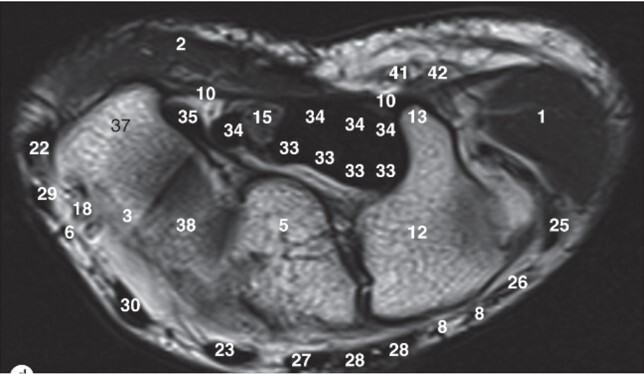

13

Q

Label 5,12,13,37,38

A

5=Capitate

12-Hamate

13=Hook of Hamate

37=Trapezium

38=Trapezoid